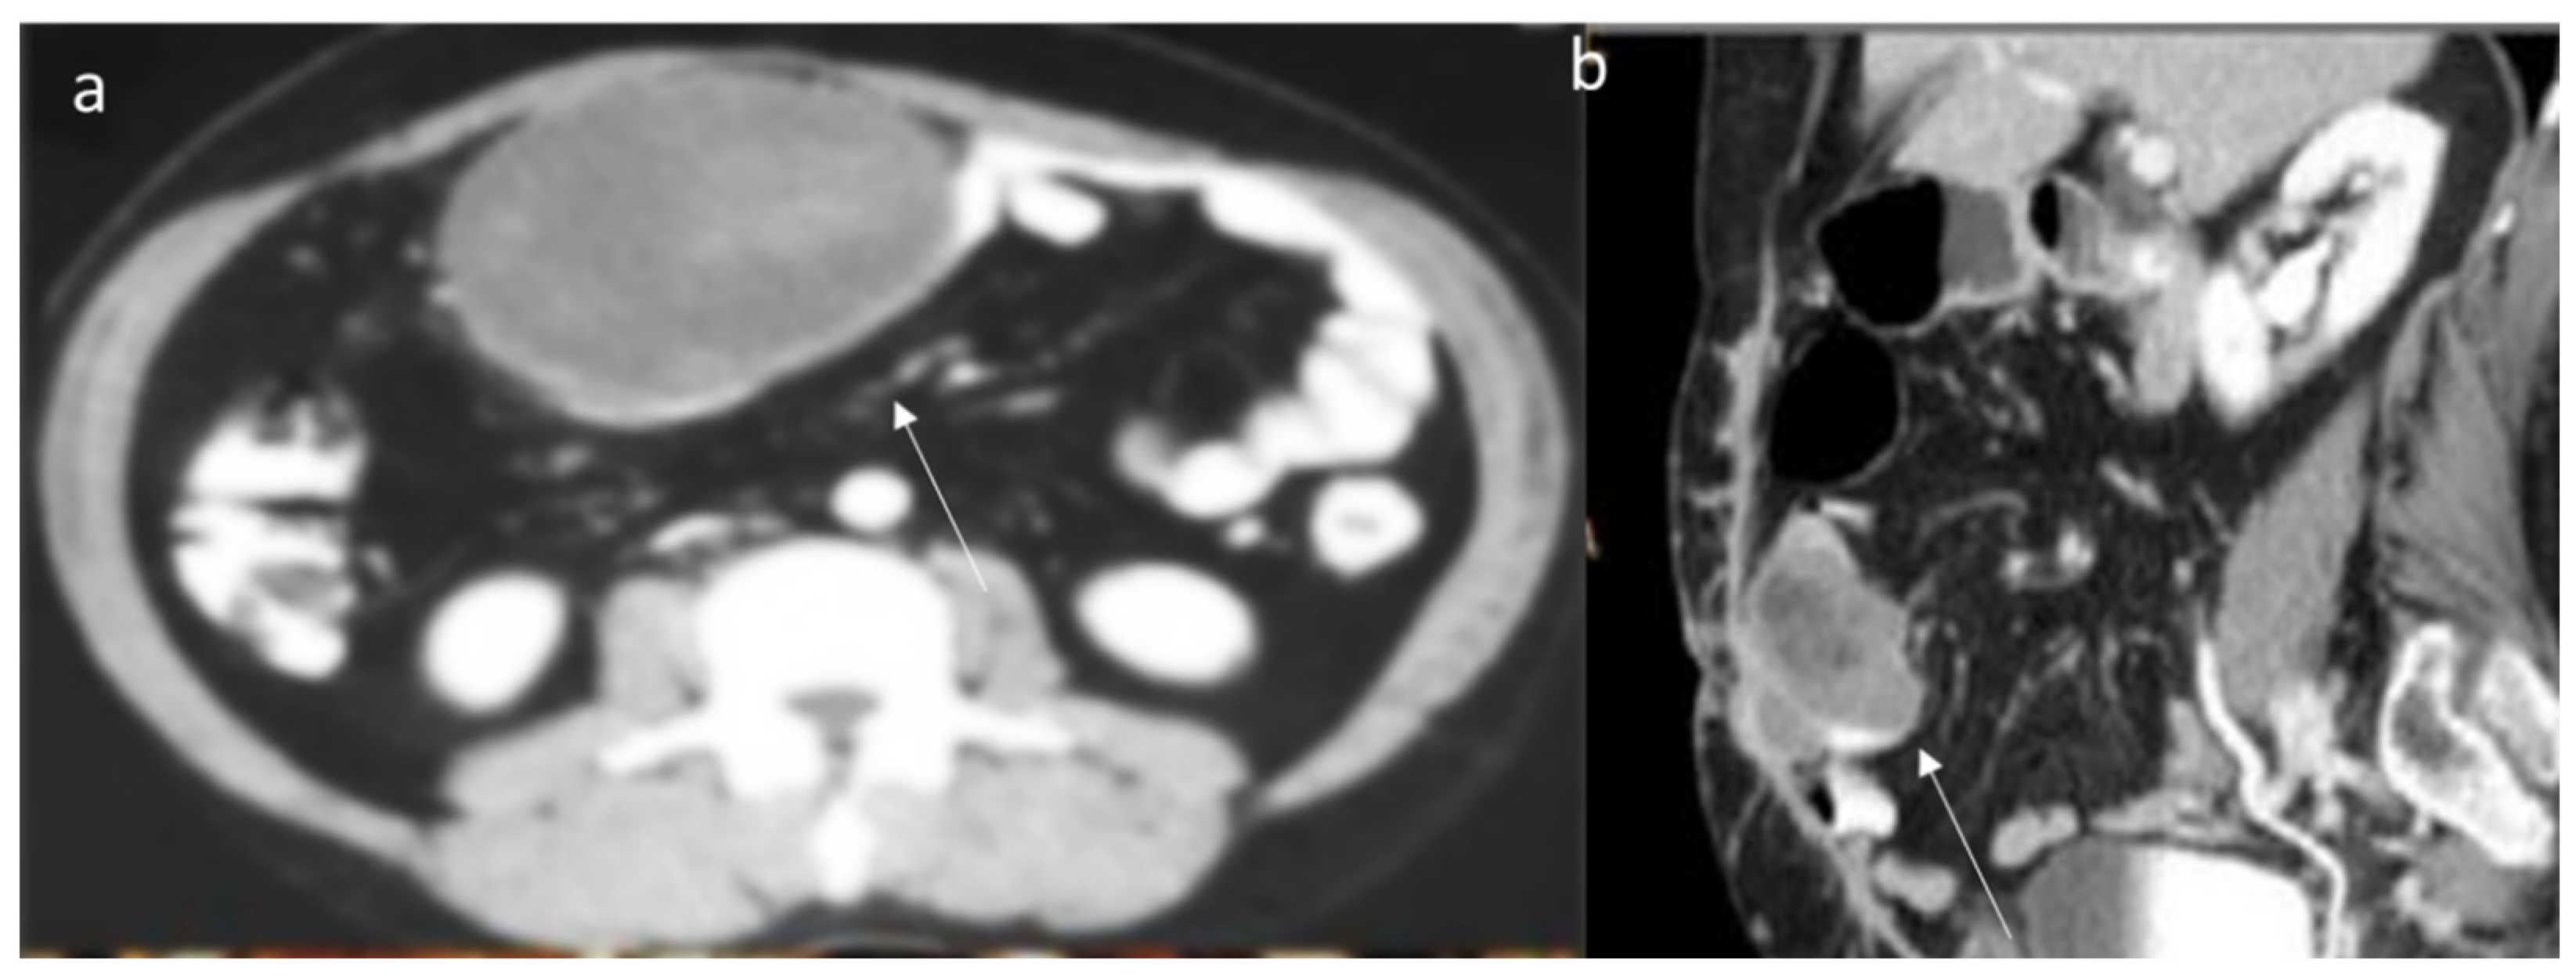

6. Computed Tomography Assessment